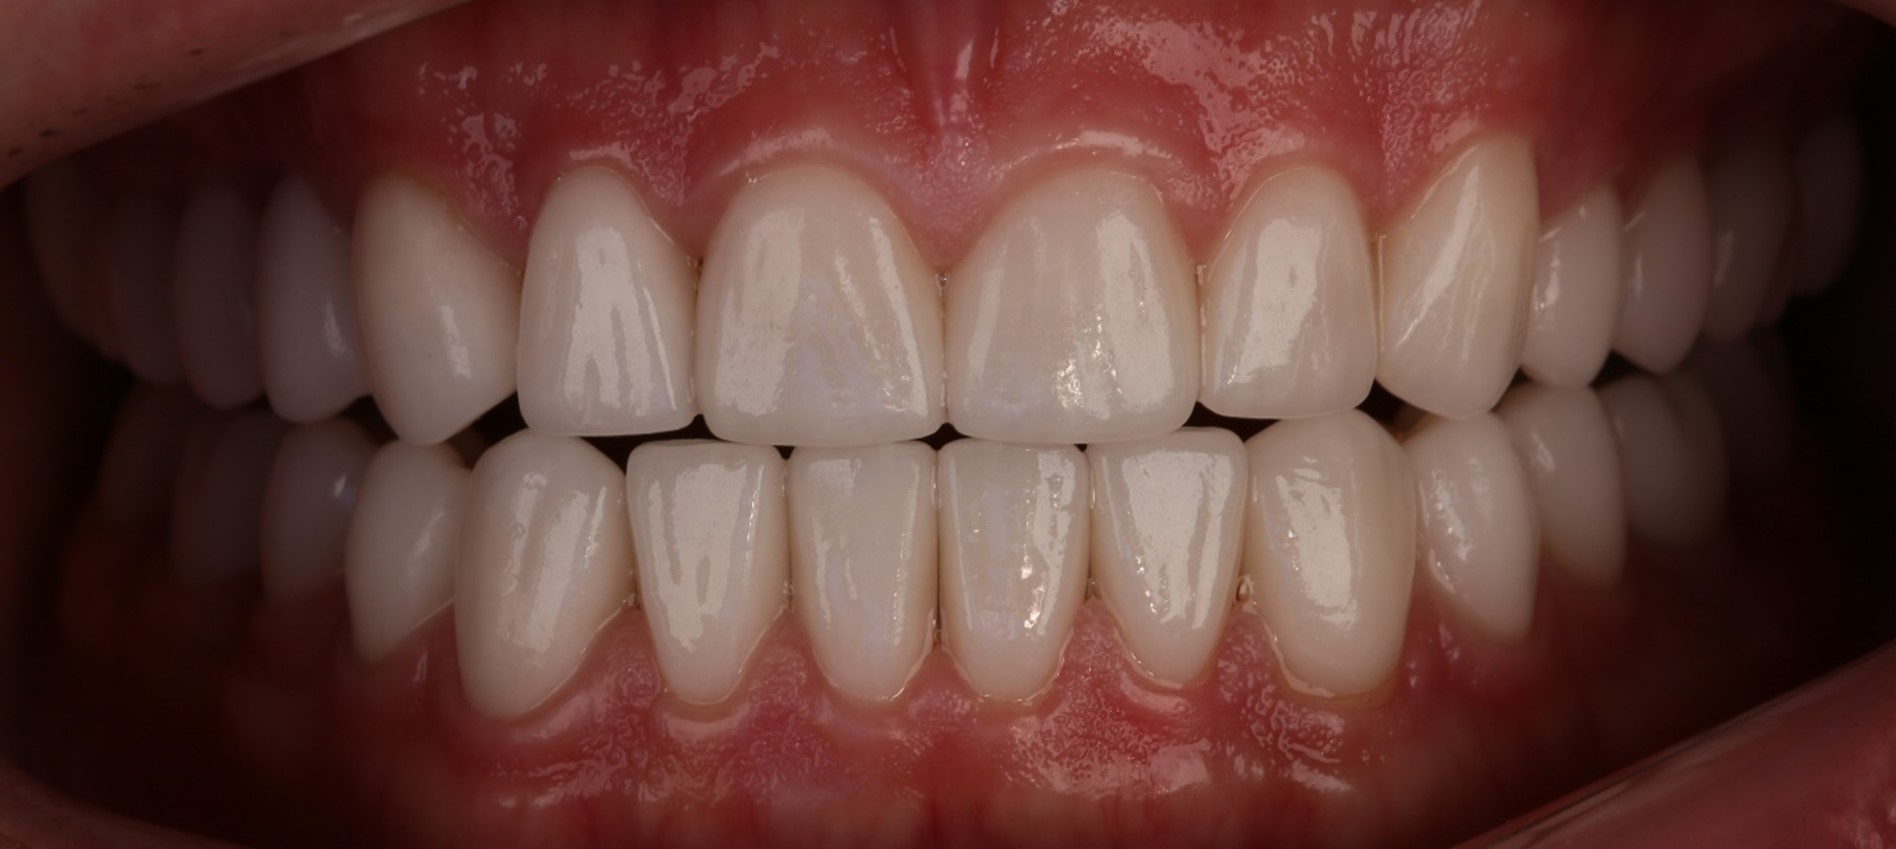

Дальше случилось самое интересное. Мне очень понравились мои новые зубы, особенно учитывая исходные данные. Но Леван Зурабович посмотрел, подумал и внезапно заявил: «Нет, давайте-ка мы поменяем за наш счёт верхние передние зубы, что-то они мне не нравятся». И мне бесплатно поменяли шесть коронок на более красивые.

Первые зубы были более короткими и плоскими, а новые — подлиннее и с более выраженными клыками. Тогда я вообще ничего в этом не понимал, но очень удивился и сказал: «ОК, ребят, делайте, что считаете нужным».

И о странном: зачем мы переделывали хорошие коронки

После всех мучений у нас получился очень неплохой результат, который кардинально отличался от исходной картинки. Но через два месяца мы сели его коллегиально анализировать и поняли, что фронтальные зубы не совсем соответствуют нашим представлениям о прекрасном. Решили их немного откорректировать и удлинить, сделать более яркими и брутальными. Финансово пациента это никак не затронуло: мы сделали всё за свой счёт. Просто потому, что так было бы правильно.

Первый вариант

После временных коронок десна достаточно сильно выровнялась, и шесть центральных зубов, от клыка до клыка, стали казаться слишком короткими. После этих изменений улыбка у Ивана стала гораздо выразительнее.